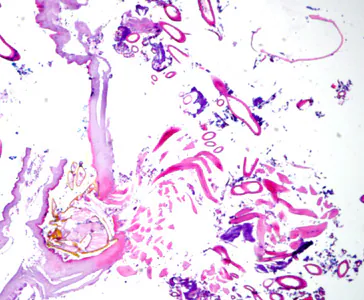

A 35-year-old woman went to her health care provider with complaints of abdominal pain, cramps and diarrhea. She told her doctor that she had recently returned from a business trip to Mexico. Stool was collected in 10% formalin and polyvinyl alcohol (PVA) for routine ova-and-parasite (O&P) examination.